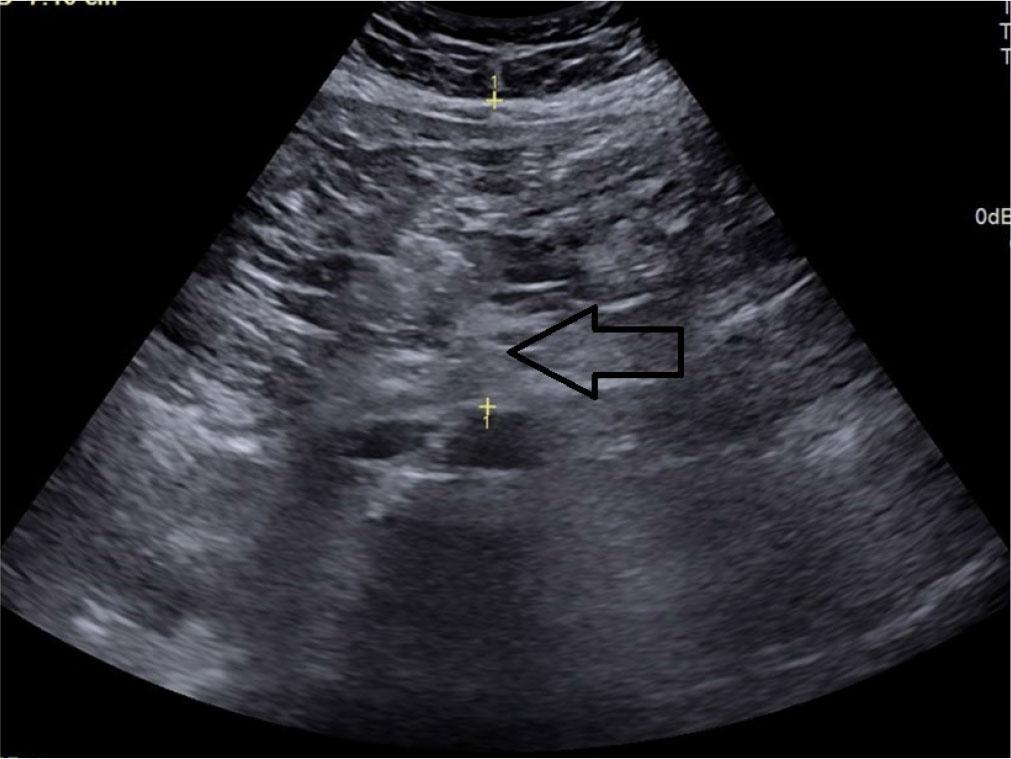

Preperitoneal fat thickness (PPFT) – the maximum thickness of abdominal fat located between the linea alba and the anterior surface of the liver capsule(21) (Fig. 2).

Transverse grey scale ultrasonography of the abdomen showing measurement of preperitoneal fat thickness denoted by calipers (arrow)